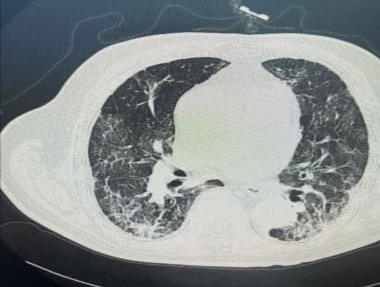

入院时CT

影像结果显示,双肺磨玻璃影,多考虑感染性病变,病毒性肺炎可能,肺水肿不能完全排外。完善相关检查,面罩吸氧下患者血氧饱和度维持在后60%左右,予呼吸机辅助通气,结合患者检验、检查、症状及体征,考虑为新型冠状病毒肺炎合并鲍曼不动杆菌感染、真菌感染,给予患者抗病毒、抗感染、抗炎、抗真菌、增强免疫力治疗后,肺部病灶较前明显吸收,脱氧状态下血氧饱和度维持在95%,在感染性疾病科医护人员的共同努力下,患者好转出院。

出院时CT